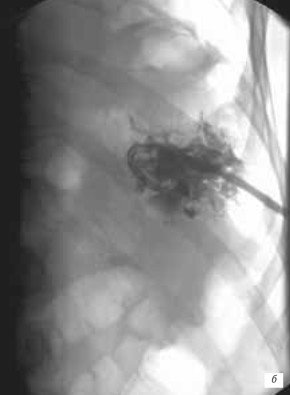

а) Поддиафрагмальный абсцесс после гастрэктомии со спленэктомией.

б) Чрескожное дренирование полости абсцесса под рентгенотелевизионным контролем.